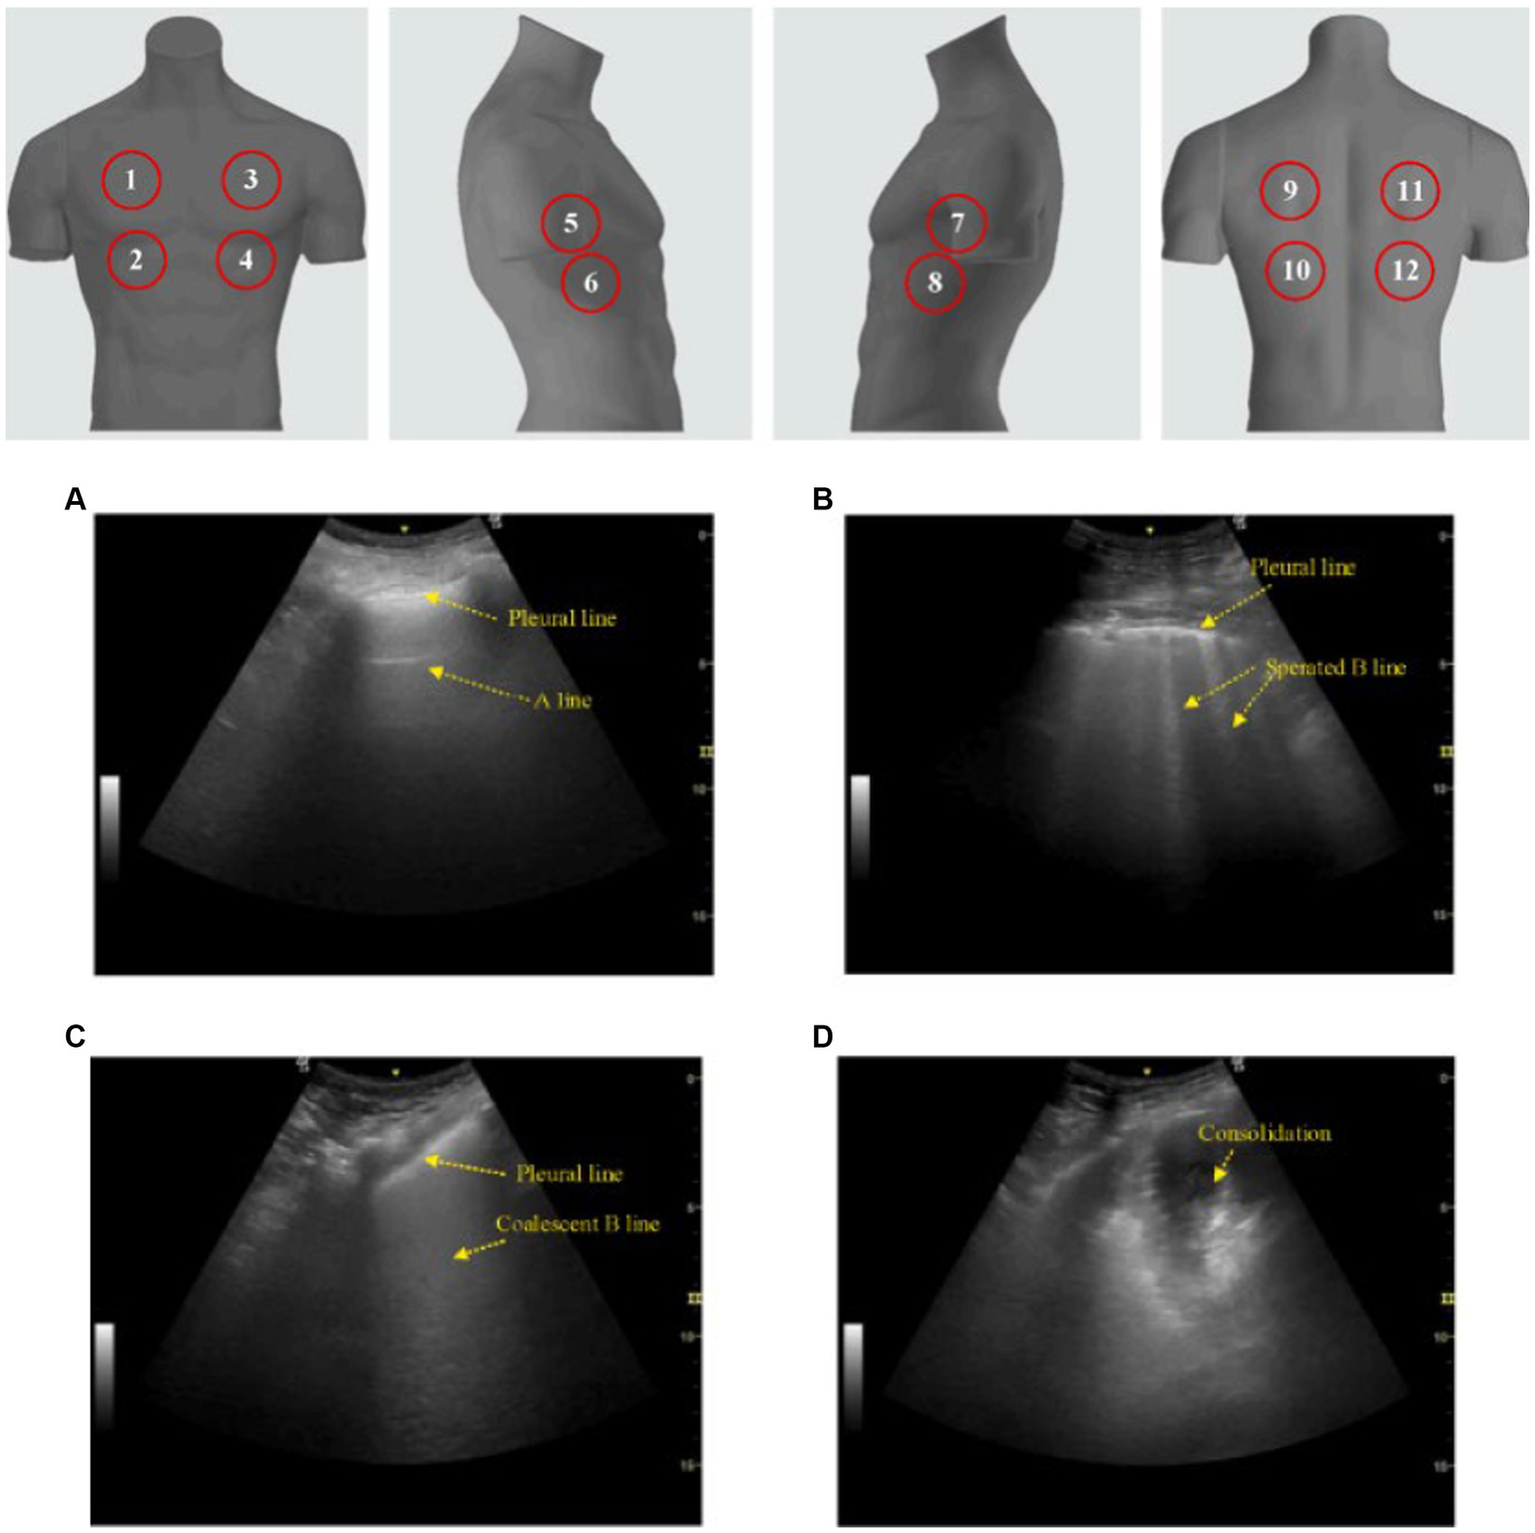

Figure 2

Lung ultrasound score (LUS). The classic LUS requires scanning 12 zones (upper image; 6 on each hemithorax) while scoring each zone from 0 to 3 based on pattern. (A) A score of 0 is a normal pattern. (B) A score of 1 requires at minimum 3 isolated or coalescent B-lines covering <50% of the screen without clear subpleural alterations. (C) A score of 2 is given when B-lines encompass >50% of the screen without clear subpleural alterations. (D) And finally, a score of 3 is made when consolidation is observed. Total scores range from 0 to 36. This image is reproduced with permission from the Elsevier Novel Coronavirus Center. No changes were made to this image (38).